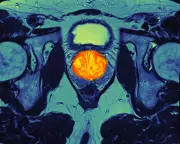

Pancreatic Cancer Early Warning Signal Found Years Before Symptoms

Scientists have identified a cellular 'early warning signal' for pancreatic cancer that appears years before symptoms, potentially enabling earlier detection and treatment of this deadly disease.